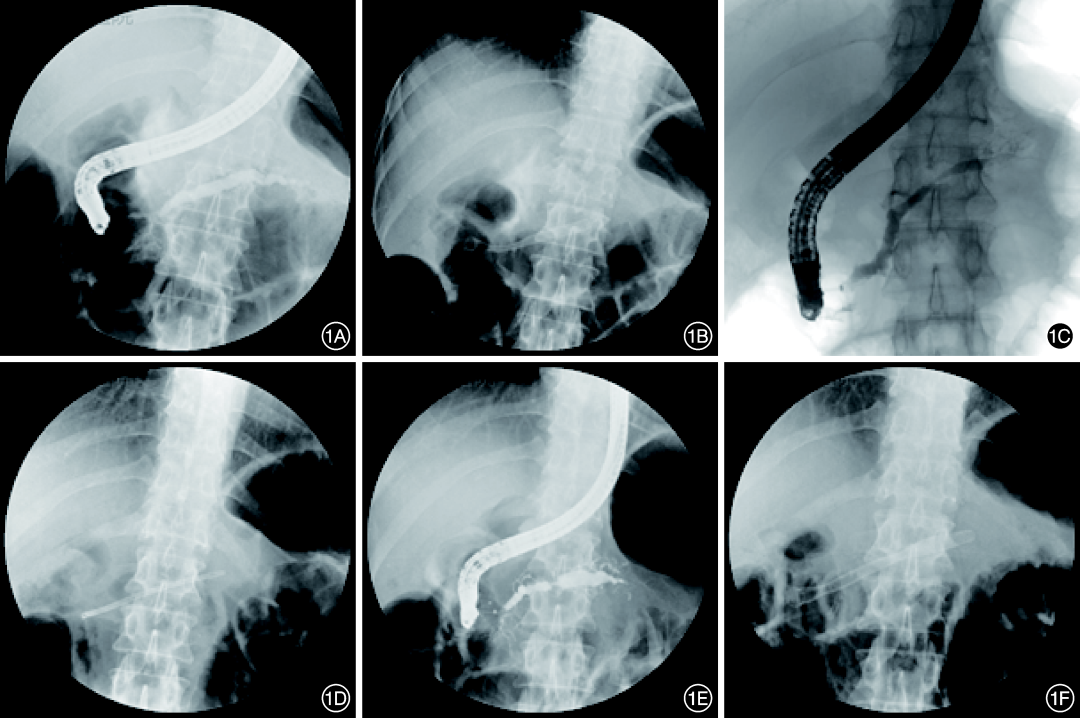

2.支架置入后远期并发症:2例患者发生支架远端移位,拔除时确定主胰管狭窄成功解除且患者无症状,未进一步内镜治疗。2例出现支架诱导的主胰管再狭窄,其中1例因支架诱导的再狭窄并不严重且患者无临床症状,未进行相关治疗;1例放置塑料支架后仍未解决,遂放置FCSEMS(图1)。

1 全覆膜自膨式金属支架置入后诱导的新胰管狭窄及治疗 1A:经内镜逆行胰管造影示胰头部胰管狭窄,体尾部扩张;1B:置入全覆膜金属支架;1C:拔除金属支架后胰体部出现新的狭窄(denovo);1D:置入塑料支架;1E:拔除塑料支架后胰体部狭窄较前明显加重;1F:置入全覆膜金属支架

FCSEMS诱导主胰管出现新狭窄即denovo狭窄,通常由近端支架末端引起。据报道两端喇叭样开口的FCSEMS诱导狭窄发生率为16%~27%14]。支架诱导新狭窄的机制可能是:(1)支架近端过度向外的径向压力和轴向力引起缺血性损伤;(2)支架的设计形状也是一个原因,比如末端为喇叭口状的支架容易损伤胰管产生狭窄;(3)孔径大的支架容易诱导新狭窄。因此临床上根据患者胰管形态选择合适支架可以预防再狭窄。一项研究纳入18例难治性胰管良性狭窄患者,置入直径6mm的FCSEMS,结果发现无一例发生再狭窄,可能是由于直径6mm的支架优化了FCSEMS的径向力,同时研究者在金属支架内再置入塑料支架,起支撑作用,可以提高金属支架的适形性,减少金属支架近端的过度轴向力,从而减少胰管角度变化,减少对胰管的损伤而预防再狭窄3]。一般对于支架诱导的新胰管狭窄,球囊扩张或塑料支架可以解决,但也有加重的病例发生。Lee等15]研究改良的非喇叭样开口的FCSEMS(具有中心鞍座部分,直径比近端和远端的直径小2mm)治疗难治性胰管良性狭窄,结果25例患者无一例发生支架诱导的新狭窄,仅4%发生移位。本组18例患者中17例选用了直径8mm支架、1例选用10mm支架,发生支架诱导的新狭窄2例,1例由于发生比较轻的再狭窄且无临床症状,进行随访观察,另一例因支架诱导的再狭窄相对严重,给予塑料支架治疗,半年后拔掉塑料支架发现狭窄加重,遂给予FCSEMS。